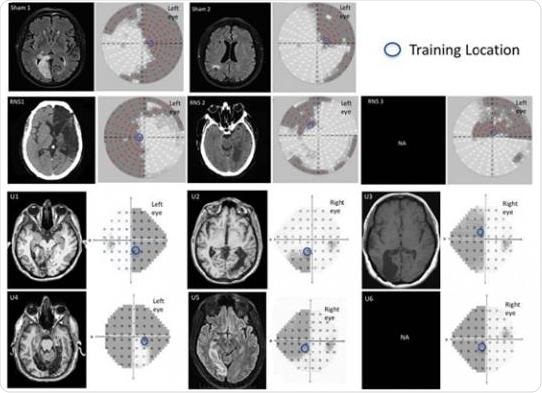

Neuroradiological images and visual perimetries of CB patients. All patients sustained damage of early visual areas or the optic radiations resulting in homonymous visual field defects as shown by the visual field perimetries, next to each brain image. Credit: Herpich et al., JNeurosci (2019)